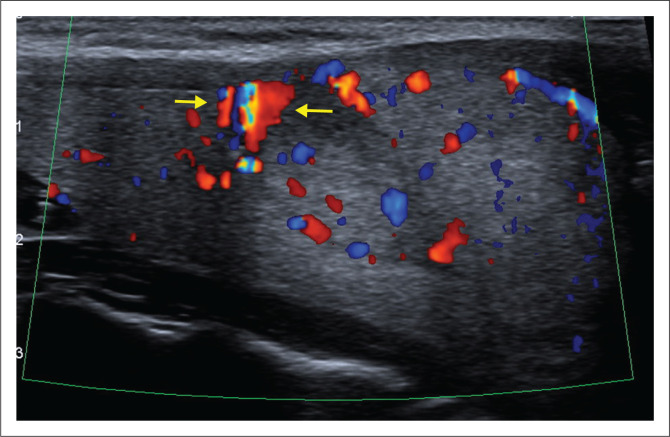

Thyroid gland vascular proliferations pose a challenge to pathologists, radiologists and surgeons. This is illustrated in the case of a 36-year-old woman who underwent a diagnostic thyroid lobectomy for a suspected follicular neoplasm according to cytology. Histological diagnosis confirmed a follicular adenoma as well as a cavernous haemangioma or venous malformation.

Contribution: Thyroid vascular lesions are rare. Evolving nomenclature and application of the International Society for the Study of Vascular Anomalies classification are discussed. Pertinent radiological clues are highlighted to pre-empt the diagnosis and avoid potential surgical complications.